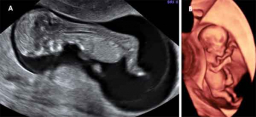

A lo largo del embarazo, el médico te recomendará una serie de pruebas diagnósticas para asegurarse que tu hijo se desarrolla correctamente, como la ecografía. Otras solo se prescriben cuando el ginecólogo sospecha que algo puede ir mal y necesita más datos para corraborarlo, como la amniocentesis o el control del bienestar fetal. Te contamos cómo y cuándo se realizan.